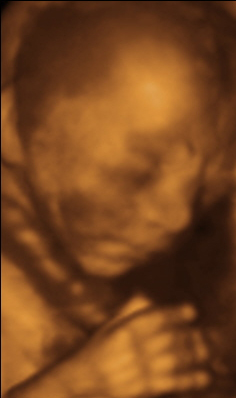

Cuando veas a tu fetito durante la ecografía de este mes notarás un sustancial cambio respecto de su aspecto en el primer trimestre. Notarás cómo ha crecido hasta superar los 25 centímetros. Sin embargo, su peso te puede parecer escaso, ya que apenas alcanzan los 250-300 gramos al final de este mes, puesto que apenas han adquirido cúmulos grasos. Su aspecto es más proporcionado y la cabeza ya no es tan grande como en la primera ecografía, aunque todavía supone casi un tercio del tamaño de todo el cuerpo.

Dado el tamaño que ya alcanza y su capacidad para moverse, tu feto comienza a hacerse notar. Es una etapa en la que, además de estar activo, tiene una relativa facilidad de movimientos y es habitual que cambie de posición. Sus movimientos ya no son tan bruscos, sino que cada vez se van haciendo más ordenados e individualizados. Comienzan a diferenciarse la alternancia entre ciclos de reposo y actividad, que serán muy característicos del feto a partir de este momento.